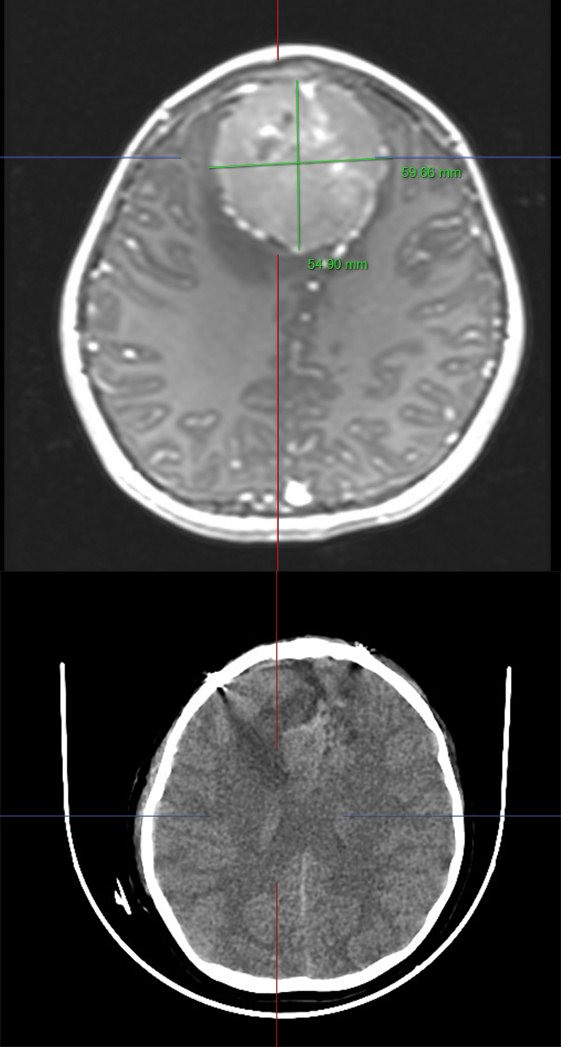

Các bác sĩ đã hội chẩn, tiến hành đánh giá xác định khối u nằm vị trí đường giữa, phát triển sang 2 bên bán cầu đại não, kích thước 62x52x50 mm, xâm lấn làm tắc hoàn toàn xoang tĩnh mạch dọc trên.

| Kích thước khối u trên phim chụp - Ảnh BVCC |